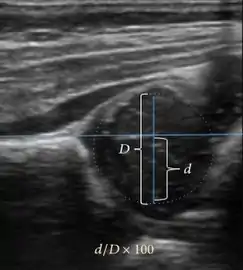

Ultrasound allows categorizing pediatric hips, according to Graf’s criteria, in four main types: normal, immature, and dysplastic (subluxed and dislocated). This classification is based on measurements of the acetabular inclination angle (alpha), cartilage roof angle (beta), and infant age. The femoral head coverage can also be determined by dividing the length of the femoral head covered by the acetabular fossa and the diameter of the femoral head. Its lower normal limits are 47% for boys and 44% for girls (Figure 11).[1]

Figure 11:

Useful ultrasound measures in neonatal hip sonography, alpha and beta angles.[1]

Measurement of femoral head coverage.[1]